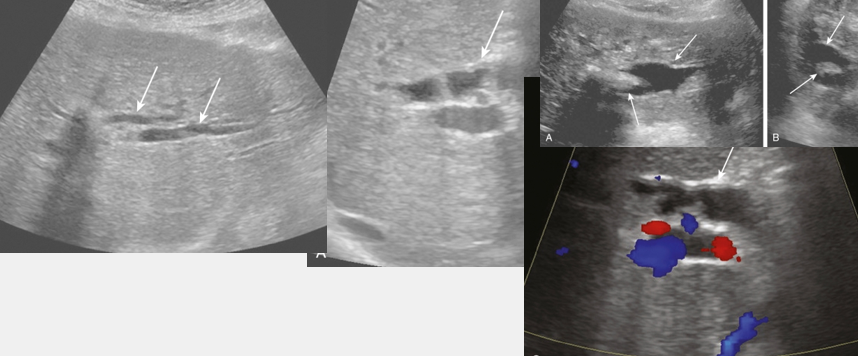

HA thrombosis

HAT

hepatic artery stenosis (HAS)

HA to PV fistula (AVF)